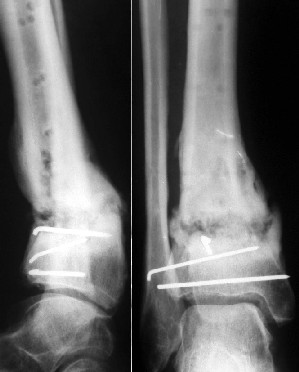

Нашел в комп-ре схожий случай:

1) з/репозиция, 2) фиксация 2 спицами, 3) аппарат, 4) фиксационные

спицы удалены...

См. аттачт.

А можно было наложить аппарат и по поводу ложного сустава...

По крайней мере не было бы укорочения (пусть и в 2 см)...